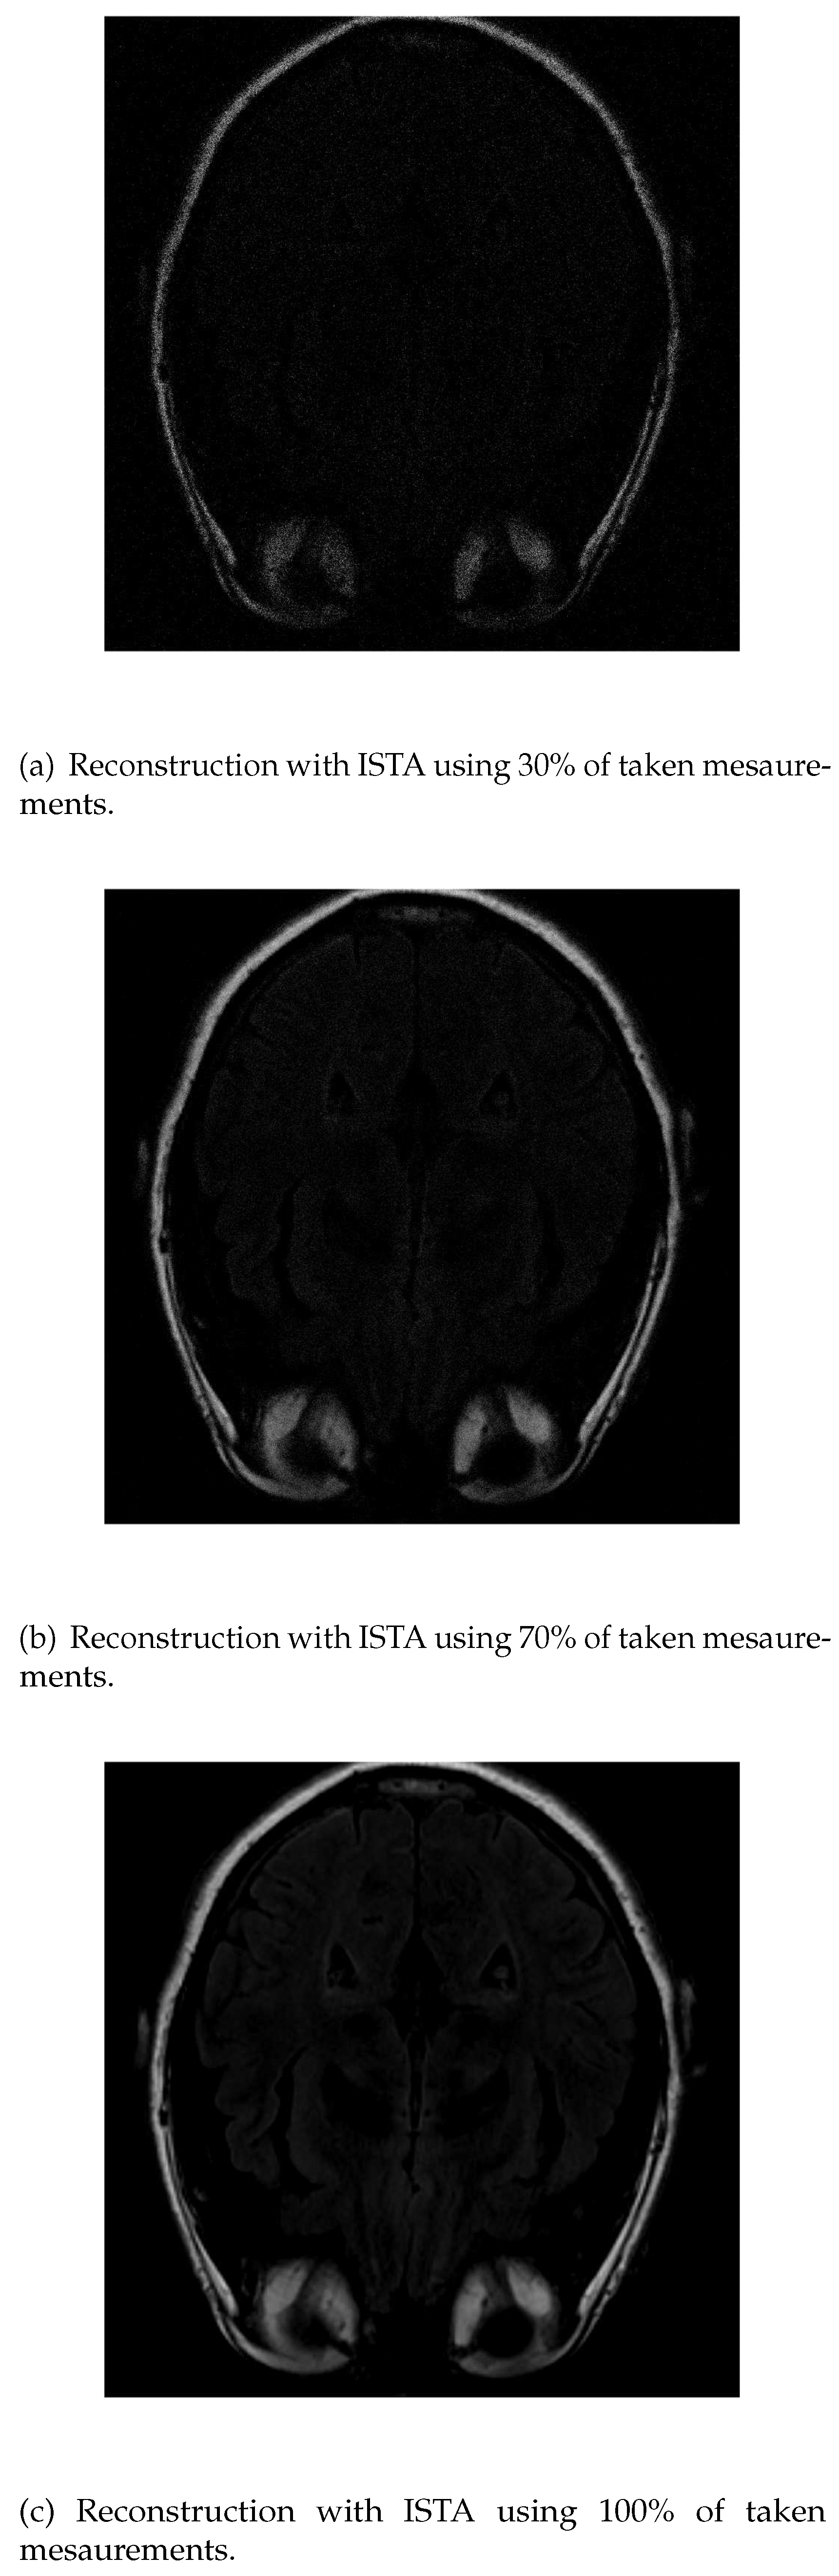

As in IRLS, the ISTA algorithm detects first the areas of highest intensity in the first measurements without distinguishing white matter (Figure 5a). If the number of input data is increased, the resolution of the edges increases but it is still difficult to differentiate the white matter (Figure 5b). Finally, the resolution increases until the shape of the fat is detected (Figure 5c).

Figure 6. Reconstruction of the image in Figure 3 using ISTA with 30 % (a), 70 % (b) and 100 % (c) of taken measurements.